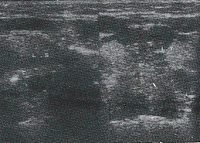

原发性舌癌的二维超声显像特征 本组结果显示原发性舌癌超声显像表现依瘤体大小不同及病变类型不同而异。瘤体小者表现为境界清晰、内部回声尚均匀的低回声结节(图1);瘤体大者(T2期以后)多表现为边缘不光滑、形态欠规则、回声欠均匀的低回声团块。伴瘤体跨越舌中线者,则声像图上舌中隔线连续中断或消失(图2左);溃疡型者,声像图上溃疡面呈高或强回声光点、光斑(图2右);浸润型病灶侵及口底舌外肌者声像图上低回声病灶超出主舌块区(图3),受侵处口底、舌外肌声像失常,舌活动度亦受限。

病灶呈低回声结节,位于舌腹面,未侵及口底

图1 左舌尖小鳞癌 左为舌尖纵切面,右为舌尖横切面